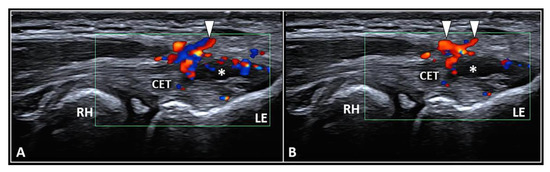

3.3. Enthesis Injection

| Enthesis | Tendon-bone interface | Intralesional injection and/or fibrocartilage plate abrasion |